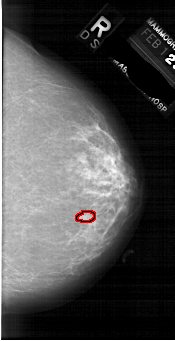

A_1739_1.LEFT_MLO

LEFT_MLO LINES 6871 PIXELS_PER_LINE 3511 BITS_PER_PIXEL 12 RESOLUTION 43.5 NON_OVERLAY

FILE: A_1739_1.RIGHT_MLO.OVERLAY

TOTAL_ABNORMALITIES 1

ABNORMALITY 1

LESION_TYPE MASS SHAPE LOBULATED MARGINS CIRCUMSCRIBED

ASSESSMENT 3

SUBTLETY 1

PATHOLOGY BENIGN

TOTAL_OUTLINES 1

BOUNDARY